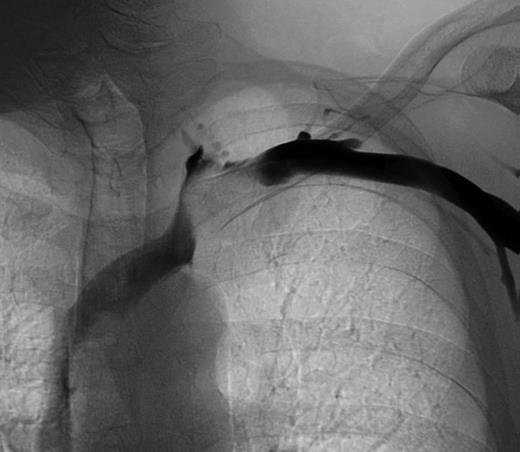

Phlebography reveals a compression of the left subclavian vein.